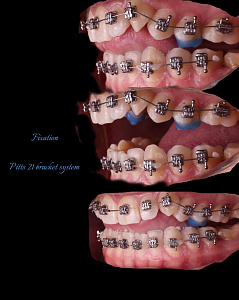

Гегиров Амир Артурович (@amir__ortodont)

Врач-ортодонт

#repost от @amir__ortodont

Была проведена полная фиксация брекетов на обе челюсти, установлены дуги и дополнительные элементы для запуска контролируемого перемещения зубов. Уже с первых месяцев лечения начинается работа над выравниванием зубных рядов, подготовкой места для правильного положения клыков и коррекцией прикуса.

В данном случае наблюдается выраженный дефицит места для клыков, поэтому лечение будет проходить поэтапно и с использованием дополнительной опоры. Каждый элемент системы работает на прогнозируемый и максимально эффективный результат.

Была проведена полная фиксация брекетов на обе челюсти, установлены дуги и дополнительные элементы для запуска контролируемого перемещения зубов. Уже с первых месяцев лечения начинается работа над выравниванием зубных рядов, подготовкой места для правильного положения клыков и коррекцией прикуса.

В данном случае наблюдается выраженный дефицит места для клыков, поэтому лечение будет проходить поэтапно и с использованием дополнительной опоры. Каждый элемент системы работает на прогнозируемый и максимально эффективный результат.